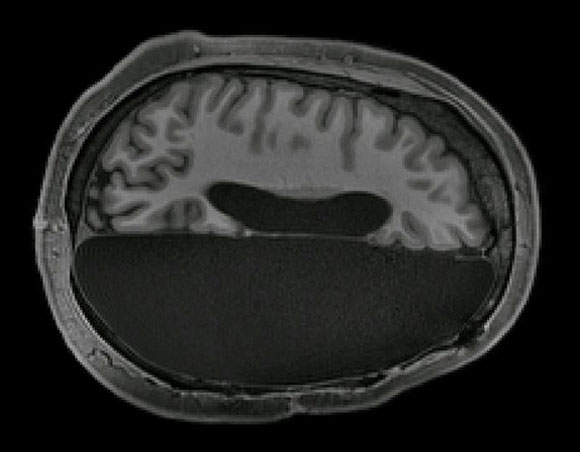

في الصّورة: إحدى العلاجات الحادّة. مسحٌ دماغيٌّ لشخصٍ خضع لإجراءِ -hemispherectomy استئصال نصف الكرة الدّماغية | Caltech Brain Imaging Center